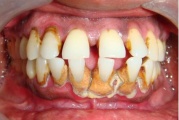

Krooniline parodontiit

Krooniline parodontiit on mikroobide poolt põhjustatud hammaste tugikudede põletik, mille tulemusena tekib progresseeruv alveolaarluu (nähtav röntgenograamil) ja periodontaalligamendi destruktsioon, igemetaskute moodustumine, igeme retsessioon või mõlemad kahjustused kombineeritult. Loe edasi »

- igemed veritsevad (19)

- igemed punetavad (21)

- ige on paistes (mädapunn)

- igemed on tursunud/vohavad (17)

- igemepiir on taandunud (3)

- luu destruktsioon (5)

- hammaste asukoha muutus (5)

- puudulik suuhügieen (5)

- igemepealne hambakivi (5)

- igemealune hambakivi (4)

- vahed hammaste vahel (5)

- halb hingeõhk / suu haiseb (12)